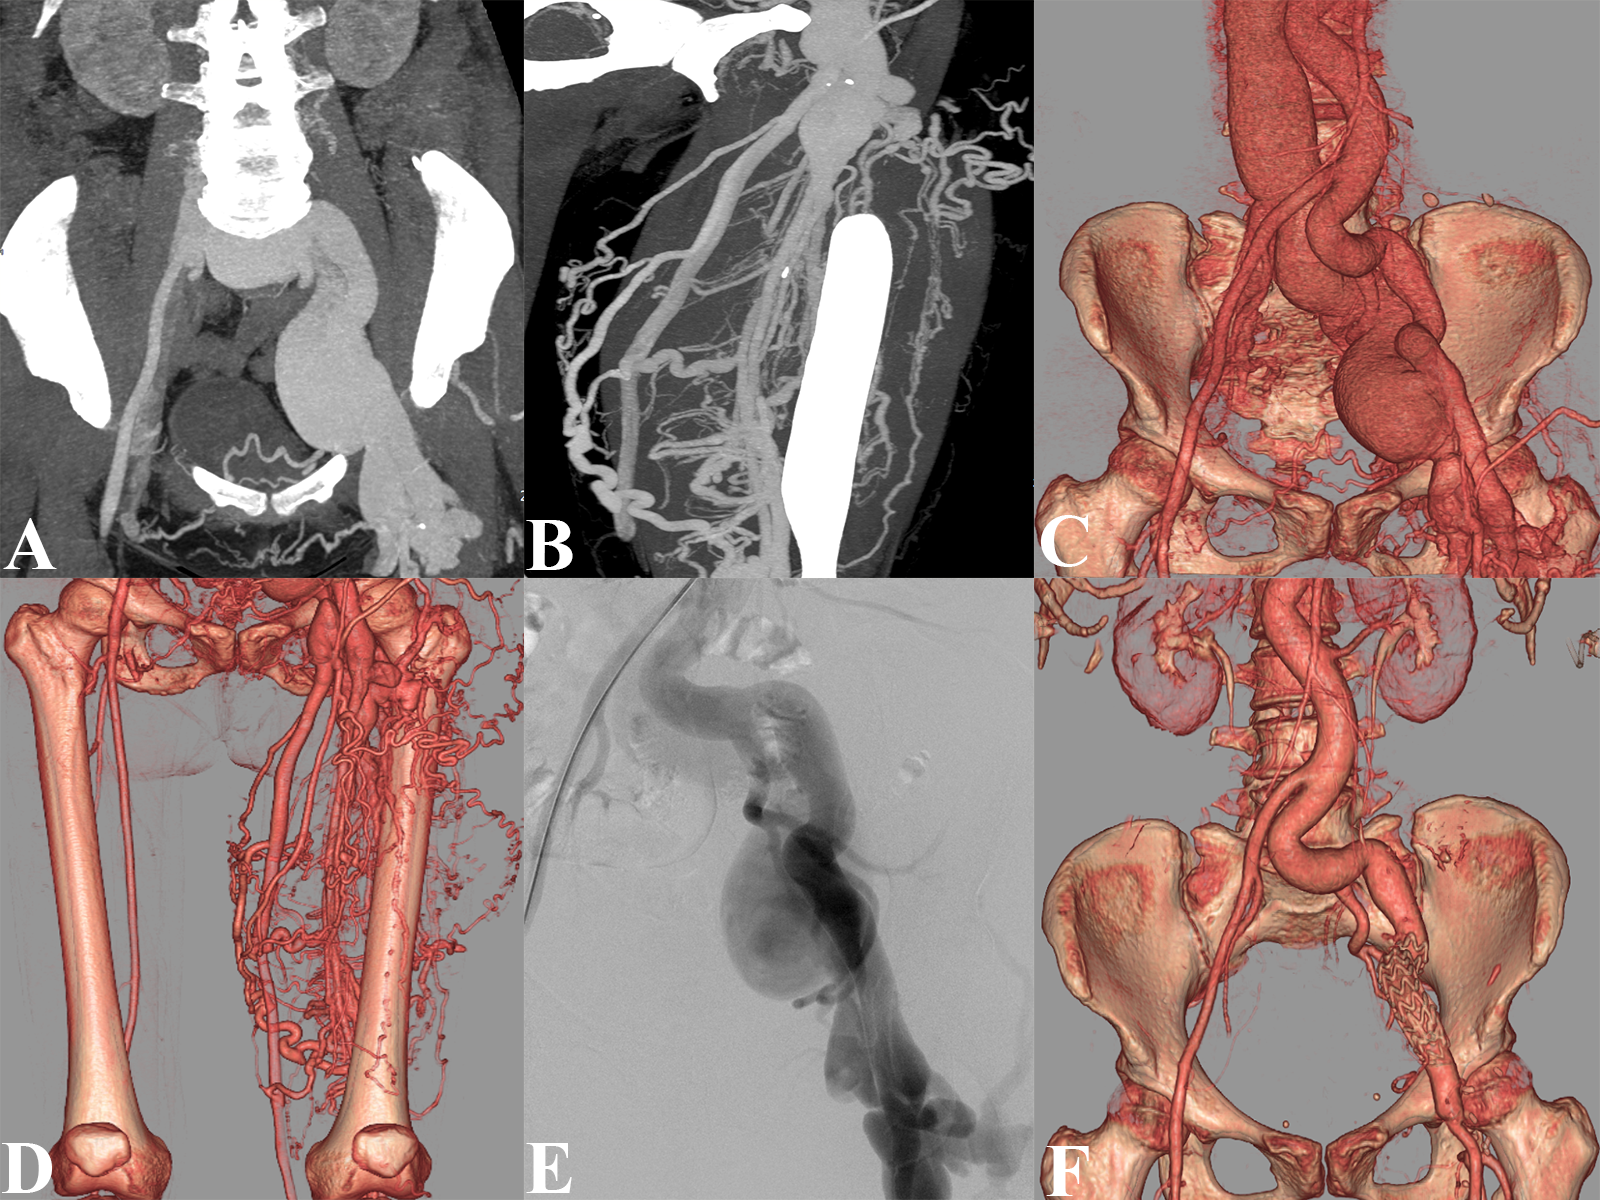

A 53-year-old woman presented with shortness of breath and fatigue for 1 week. The patient had a medical history of left thigh trauma for more than 20 years. Cardiac auscultation indicated a grade 3/6 systolic murmur audible in the aortic valve auscultation zone. Laboratory examination revealed an N-terminal fragment of the prohormone natriuretic peptide level of 2558 pg/mL (reference range<125 pg/mL). Computed tomography angiography (CTA) images suggested a left external iliac arteriovenous fistula (AVF) and a giant iliac vein aneurysm (Figure A, B), and an AVF with extensive tortuous and dilated venous collateral pathways (Figure C, D). Left lower extremity arteriography confirmed the multiple left AVFs (Figure E, Video).

The patient was successfully treated with an 80 x 24-mm Endurant stent-graft (Medtronic) closure of the left iliac AVF and surgical repair of the femoral AVF. The postoperative CTA reexamination suggested that the AVF had been wholly closed (Figure F). The patient's postoperative course was clinically uneventful, and she was discharged after 5 days. At the 6-month follow-up, the symptoms were significantly alleviated.